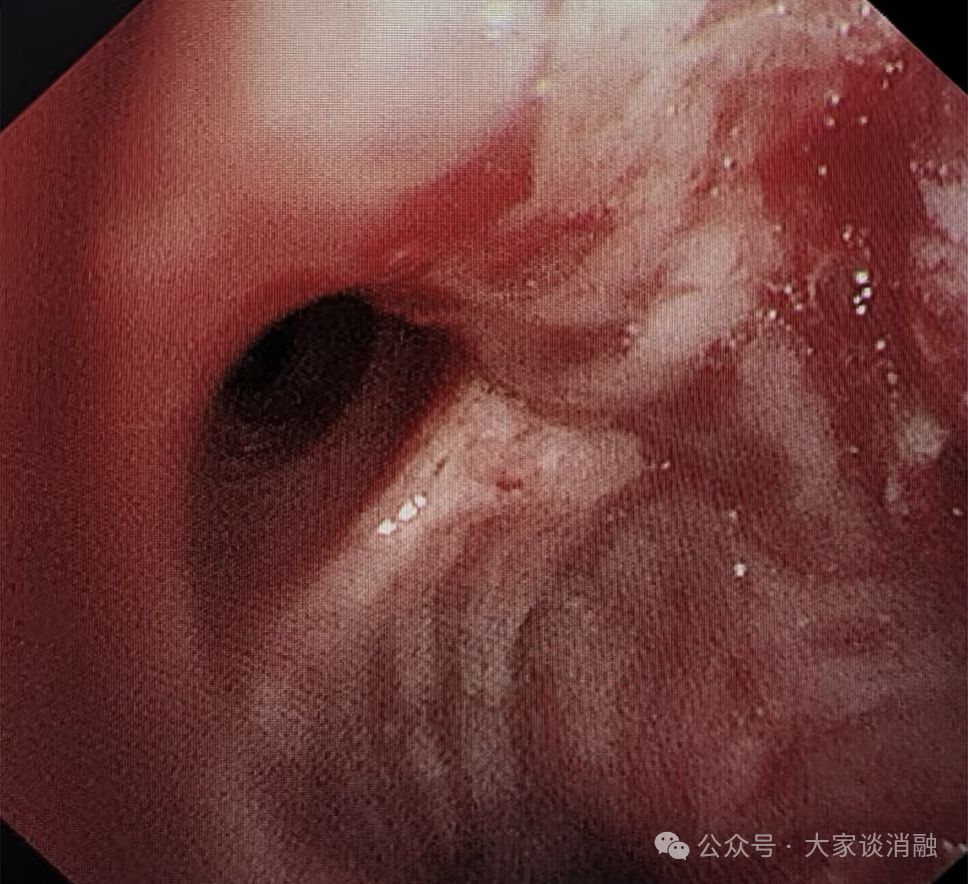

术后

10月24日,邵桂英主任团队为患者进行术后第一次局麻下清坏死组织治疗气道内的肿瘤体积进一步缩小,下叶开口管腔越来越通畅,原本严重的呼吸困难及持续咳嗽症状也明显减轻,患者及家属对治疗效果十分认可